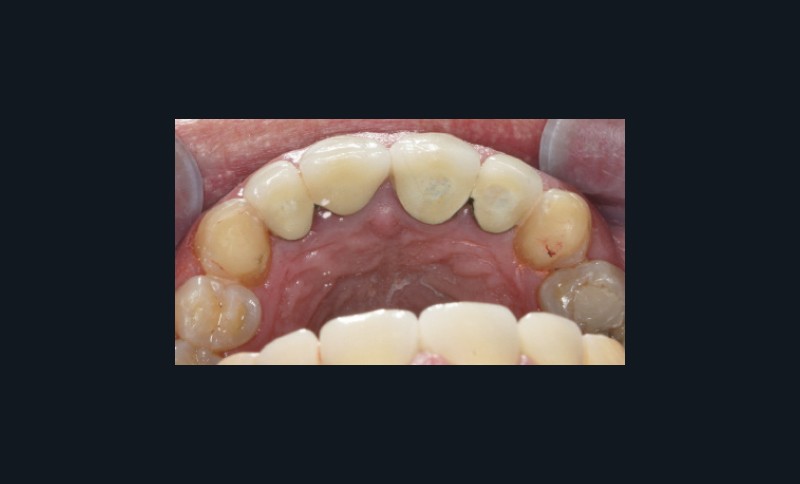

Dents : soins dentaires à réaliser sur 16, 26, 37.

Amputation mésiale de 46 ?, légères érosions.

Bruxisme : net avec attrition antérieure marquée en particulier en regard des coiffes céramiques.

Occlusion : décentrage gauche, création d’une légère béance antérieure probable conséquence

de l’atteinte de l’ATM gauche.